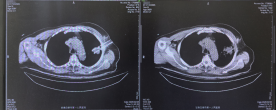

综合考虑患者病情及既往治疗情况,介入医学科团队经充分评估后,决定为其施行氩氦刀冷冻消融治疗。术中,通过CT引导精准定位病灶,利用高压氩气迅速降温至零下140℃以下,使肿瘤细胞内冰晶形成、细胞膜破裂,继而通过氦气快速复温至20℃–40℃,完成“冻融”循环,导致肿瘤组织不可逆坏死。术后影像显示病灶密度明显减低,肿瘤实性组织轮廓消失。患者术后未再出现痰中带血,恢复顺利,已于近期出院。

消融前后对比

术前术后对比